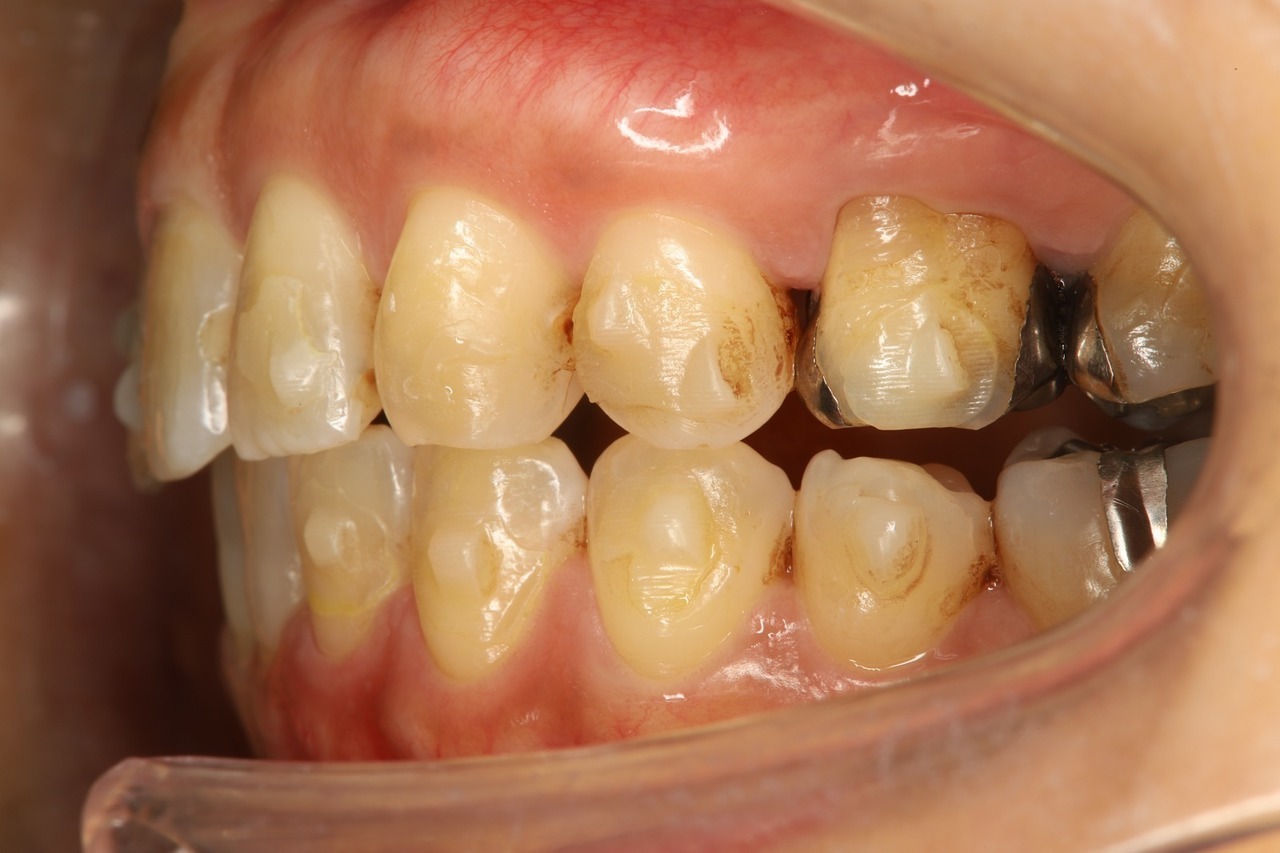

歯を並べるスペースの確保のために歯を削りすぎた結果、歯並びが完全に治らず前歯がすきっ歯になっています。

奥歯の上下が噛み合わなくなっています。これではお食事をとるのにも不自由します。

当院には、他院でマウスピース矯正を受けたものの、思うような結果が得られなかった患者さまが数多く来院されます。

この患者さまはインビザラインを4年間続けたものの、不十分な診断と治療計画によって歯を削りすぎてしまい、歯並びも咬み合わせも整わなかったケースです。